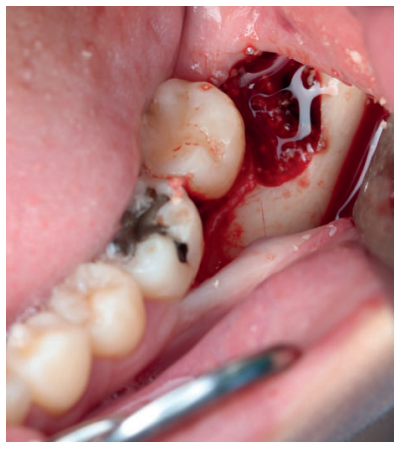

Tras obtener el consentimiento informado, se realizó un bloqueo anestésico mediante Articaína al 4% con adrenalina 1:100.000 del nervio dentario inferior y lingual, y posteriormente el nervio bucal. Se realizó una incisión festoneada lineal desde la cara distal del primer molar inferior izquierdo, hasta la cara distal del segundo molar inferior izquierdo, y se realizó una incisión oblicua hacia la rama ascendente mandibular. Tras el despegamiento mucoperióstico, se realizó una protección del nervio lingual durante las maniobras de ostectomía. Posteriormente se realizó la ostectomía necesaria para liberar el límite amelocementario del tercer molar inferior, procediendo a su luxación mediante botador recto, odontosección coronal con pieza de mano y fresa redonda de carburo de tungsteno, y exodoncia del fragmento radicular una vez retirado el fragmento coronal (Figura 2). El alveolo se lavó con suero fisiológico y se le hizo al paciente morder una gasa estéril empapada en clorhexidina al 0,12%, durante la preparación del material de injerto.

Los fragmentos coronal y radicular se limpiaron de restos de tejidos blandos, y secos, se introdujeron en la máquina Smart Dentin Grinder® (Kometa Bio, BIONER, España). Tras un ciclo de triturado de 3 segundos, y otro de tamizado de 20 segundos, el material obtenido (Figura 3) se limpió con la primera solución durante 12 minutos, y después durante 3 minutos con la segunda solución, para después transportar el material de injerto al alveolo, con presión controlada (Figura 4). Una vez compactado, se colocó una esponja de fibrina (Gelatamp® ) (Figura 5) y se suturó la herida con seda de 4/0, mediante dos puntos simples en la cara distal del segundo molar inferior izquierdo, un punto en cruz en la descarga y un punto en la papila (Figura 6). Se realizó una radiografía periapical intraoperatoria (Figura 7).